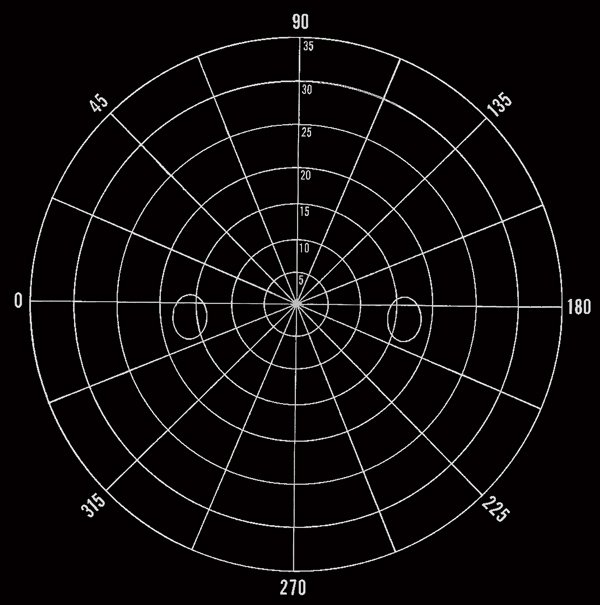

Made of the finest quality black felt. Attached one meter ribbon and occluder establishes the test distance. No need for headrest or chinrest. Double hanging rod model insures flatness.

Approximate Size: 49″ x 52″

Includes: Recording Charts, Wand, and Eight Velcro Dot Targets

*Note: Tangent Screen image is a simulated design. Product has black stitching that matches the design of the white target shown. It is up to the practitioner to make their own design.